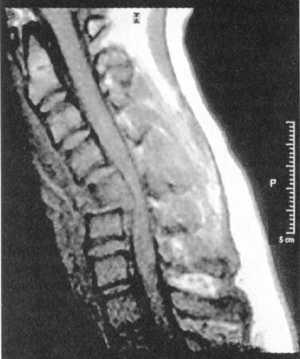

Ценную информацию о состоянии вывихнутых позвонков и спинного мозга дает

МРТ (рис. 2.6, 2.7). МРТ позволяет определить наличие зон ишемии в спинном

мозге (рис. 2.8, 2.9), состояние ликвородинамики (рис. 2.10).

Рис. 2.6. Переломо-вывих скользящий

C5-C6, позвонков со смещением тела С5 кзади с грубой компрессией спинного

мозга на данном уровне |